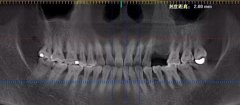

半口残根烂冠上颌咀嚼功能丧失

上颌咬合重建植入种植体后佩戴临时冠

长期缺牙骨量萎缩上下牙颌咬合关系重建

MAC数字化精确种牙定制all-on-4恢复一口好牙

活动牙致牙周疾病长期多颗缺牙骨量不足

MAC精确方案设计牙周病情稳定后完成种牙

下颌牙多颗缺失

MAC数字化精确种牙搭配冠桥减少种牙费用